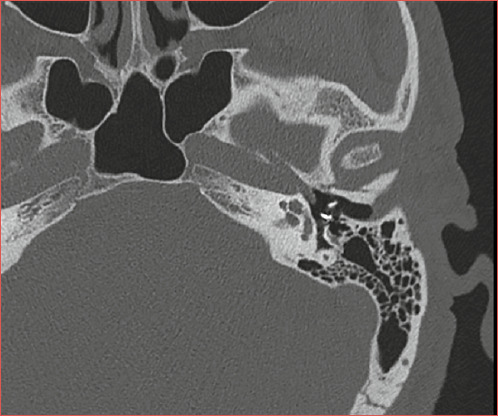

Abstract Image